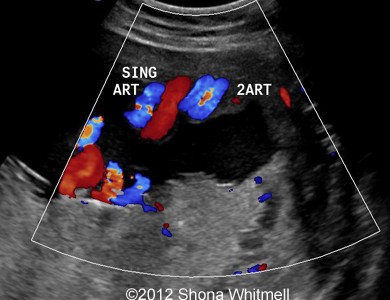

Figure 2

: 3-vessel cord and 2-vessel cord at the same plane.

Image-21